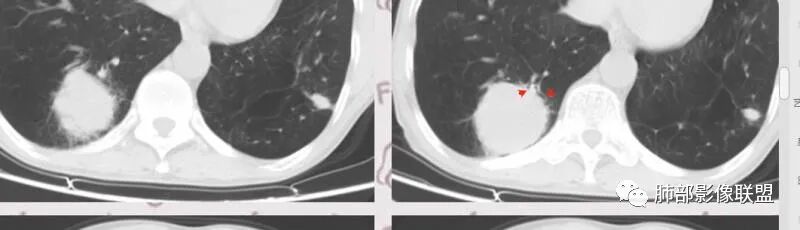

患者老年男性,因咳嗽 咳痰 背痛就诊。既往有喉及肺结核病史。胸部CT:左下肺实性病灶,边缘可见短硬毛刺,分叶,胸膜牵拉,增强可见强化,考虑肺腺癌。

老年男性,既往肺结核病史。肺气肿背景,可见钙化灶及条索影。右肺下叶胸膜类圆形占位,边界清晰,内部可见边界清晰的坏死区,轻度强化,考虑为结核可能;左肺下叶结节,可见分叶,毛刺,胸膜牵拉,增强可见强化,考虑为恶性,腺癌可能。

左肺肺气肿,双肺多发结节,上肺多发纤维索条影及钙化,符合陈旧性结核病变。右肺下叶结块,边缘毛糙,内部可见低密度坏死,环形强化,坏死边界清楚,考虑脓肿,OP。左肺下叶结节,边缘可见毛刺,深分叶,边缘收缩,远端牵拉胸膜,考虑肺癌,腺癌。

老年男性,肺气肿背景,左肺下叶结节,深分叶,毛刺,胸膜牵拉,内部可见坏死,坏死边界不清,不均匀强化。右肺下叶大肿块,边缘有毛刺,多发小灶性坏死,胸膜下有侵犯,考虑恶性,左肺下叶腺癌,右肺下叶低分化鳞癌。

男,64岁,咳嗽咳痰,气喘10余年,右肺下叶软组织密度肿块影,边界清晰,边缘见细短毛刺及分叶,轻度胸膜粘连,病灶内密度不均,增强扫描看见坏死区,病灶边缘明显强化,考虑鳞癌可能。左肺下叶病灶深分叶、毛刺、胸膜牵拉,考虑腺癌可能,除外转移性病变。

双肺陈旧性肺结核,肺气肿背景。右肺下叶肿块,边缘毛糙,内部可见大片低密度坏死,环形强化,坏死边界清楚,考虑鳞癌。左肺下叶结节,边缘可见毛刺,深分叶,有收缩,有膨隆,胸膜牵拉,考虑腺癌。

左侧分叶,胸膜凹陷明显

1.左侧分叶深一些

左侧胸膜凹陷

主要征象:病灶分叶不明显、较光整,局部胸膜栽赃,支气管门口堵塞,有推移迹象;增强后坏死明显,内部囊变坏死边缘部分清楚、部分不清楚,病灶内可见血管,局部稍毛糙,实性部分强化较明显,总体考虑恶性病变。一部分征象指向鳞癌(支气管截断、坏死较多,病灶内血管破坏),但又有肉瘤的一些特点(病灶较大,缺乏分叶,坏死边界清晰),要考虑到肉瘤样癌。

3、本病好发于60岁以上的老年男性,多数有吸烟史。周围型多于中央型,病灶边缘较清楚,多数光整圆钝,部分可见浅分叶,少数有毛刺,无胸膜凹陷征出现。CT平扫时呈软组织密度,较小的肿块密度较均匀,肿块较大时中央常出现坏死。增强扫描肿块多呈斑片状不均匀强化,而肿瘤周边厚薄不均的囊壁样强化较具特征性。周围型多数位于胸膜下,常常侵犯胸膜或胸壁。